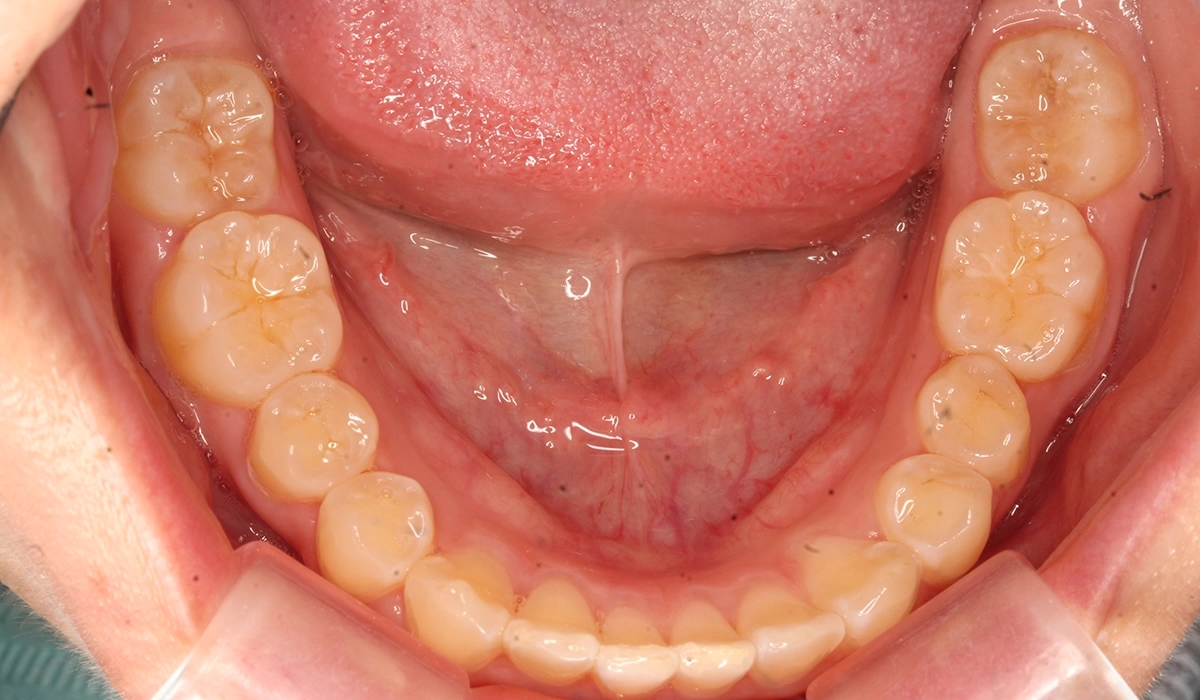

術前:下顎

術後:下顎